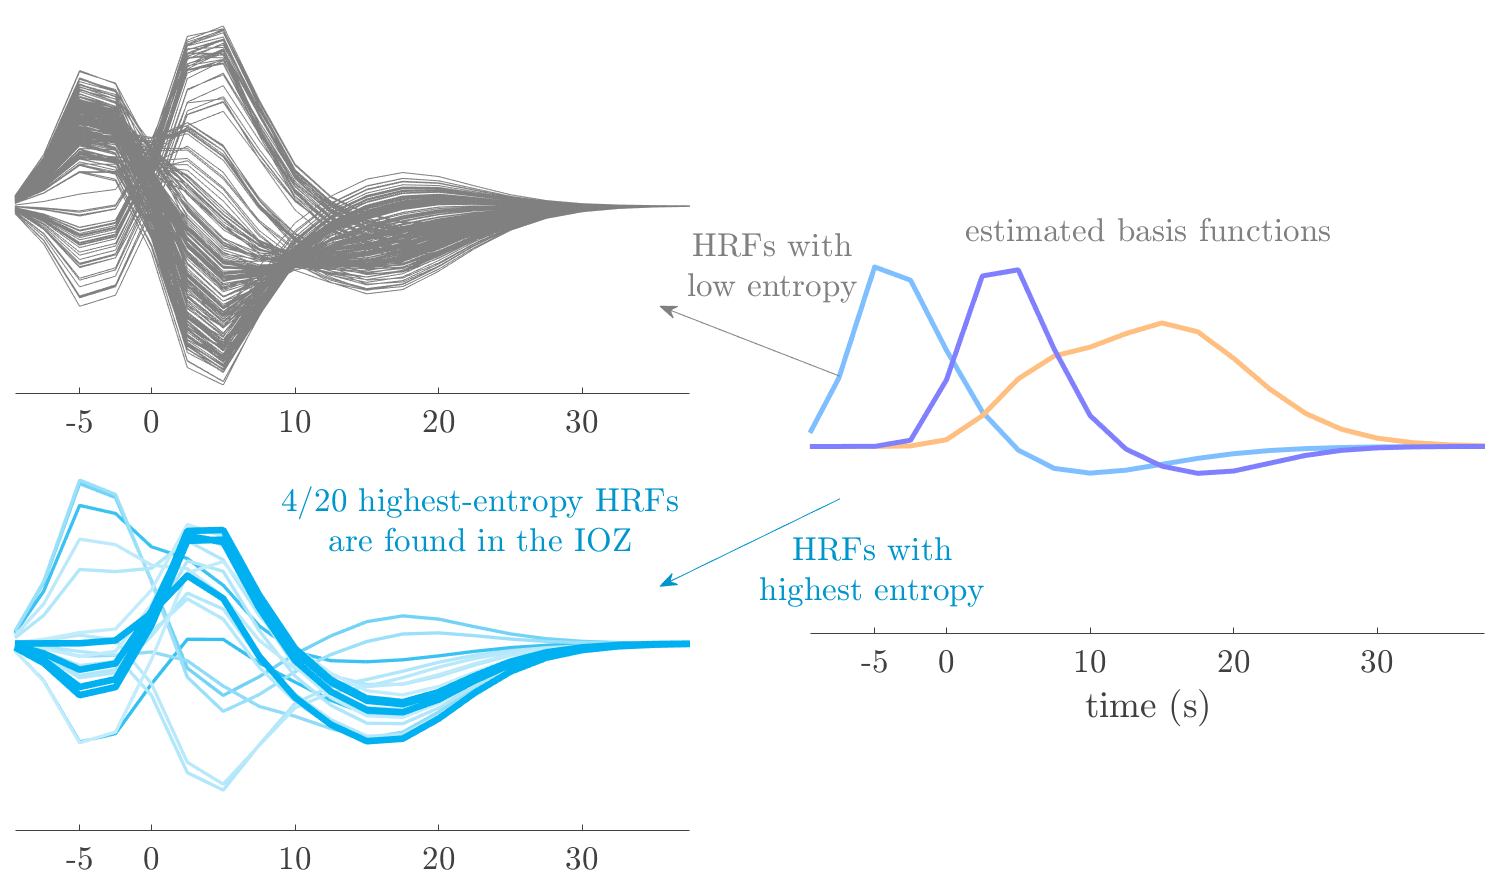

Patient 2

We analyze the solution with sources, and show the results in Figure 3 and 4. As for patient 1, we found a source which is strongly correlated to the MWF envelope, and which had a mostly low-frequency behavior characteristic for spikes. The topography is mostly uninformative, and does not clearly correspond to the patient’s clinical data. The third source is mostly present at both sides of the head, is very sparsely active in time, and has a high-frequency content: this is most likely an artifact due to the neck muscles. Again, there is one of the highest-entropy HRFs which belongs to a ROI in the IOZ. Now, the waveform is clearly resolved from the other HRFs, through the strong initial dip (before 0 seconds). Such a dip is sometimes observed in HRFs, but its underlying physiological mechanism is not yet fully understood. It is possible that this dip reflects altered vascular autoregulation near the IOZ (cfr. the explanation in the Section 1 of the main text), or a rapid depletion in oxygen due to IED generation (before the IED becomes visible on the EEG). Figure 4 furthermore shows that the IED-related component is significantly active in parts of the IOZ, and deactive in others. As mentioned earlier, this deactivation may or may not be due to errors in sign correction. Interestingly, the ROI with the high alteration in neurovascular coupling is distinct from both the activated and deactivated ROIs.